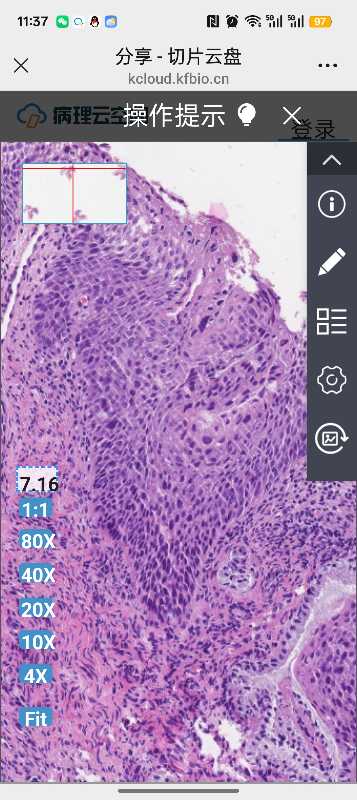

性别

女

年龄

57

临床诊断

宫颈病变

一般病史

体检

标本名称

宫颈活检

大体所见

软组织2块

hpv16+,求老师们帮忙看看是HSIL2-3吗

考虑为子宫颈高级别鳞状上皮内瘤变HSIL(CIN2-3级)

高级别CIN3